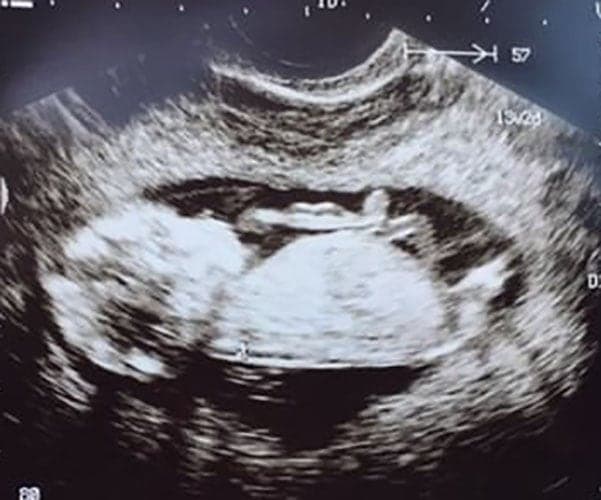

Ultraschallbilder aus dem 2. Trimester (13. bis 28. SSW)

Im 2. Trimester bekommt man oft die schönsten „Ganz-Körper“ Ultraschallbilder. Das Baby ist nun so groß, dass man alles gut erkennen kann und noch nicht zu groß, so dass es noch ganz auf das Bild passt. In dieser Zeit lässt sich meist das Geschlecht bestimmen, wobei manche Babys es einfach nicht preis geben wollen und sich immer so drehen, dass man nichts erkennen kann.